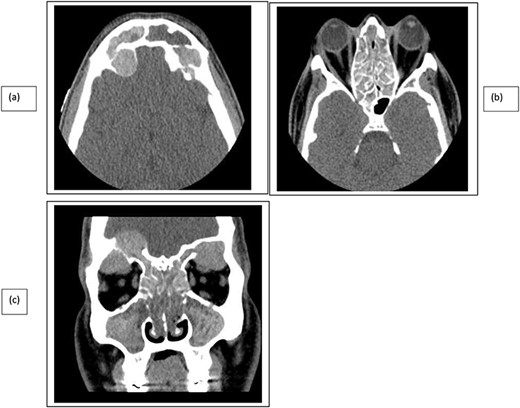

A 35-year-old Saudi male presented to our ENT Clinic with a 1-year history of progressive facial pain, headache, bilateral proptosis, anosmia and nasal obstruction. His past medical history was insignificant. Sinonasal endoscopy revealed multiple bilateral grade IV polyps, occluding the nasal cavities bilaterally. Computed tomography (CT) of the paranasal sinuses showed expansion and remodeling of the frontal sinuses bilaterally (Fig. 1). It is associated with bony dehiscence posterior wall and floor of the sinuses that results in intracranial and intra-orbital extension, respectively. The ethmoid air cells show complete opacification bilaterally with lateral bowing of the lamina papyracea. This along with the frontal sinus orbital extension lead to the clinical presentation of the orbital proptosis. The maxillary antra disease results in remodeling of the stomatal complex and obliteration of the superior two-thirds of the nasal cavities. The contents of the sinuses show mixed iso and hyperdense material. Magnetic resonance imaging (MRI) of the paranasal sinuses demonstrates the orbital and intracranial extension of the disease with no invasion of the adjacent tissues or brain parenchyma (Fig. 2). The hyperdense contents show marked low signal intensity on T2 and high signal intensity on T1.

CT paranasal sinuses axial (a, b) and coronal (c) show sinus expansion, bony remodeling and dehiscence with intra-orbital and intracranial extension. Bilateral orbital proptosis.